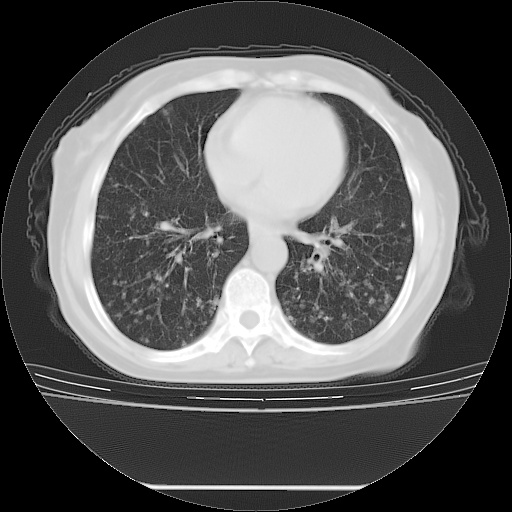

患者女性,72岁,慢性咳嗽3月余,曾抗炎治疗无效果,最近抗结核治疗约半月余,症状缓解。

ct示两肺粟粒状病灶,以两肺上叶尖后段及下叶背段分布为主;首先考虑结核。请战友们分析。

考虑 1 弥漫性泛细支气管炎, 2 结核不除外/.  有小叶中心结节 和 树芽征!!

两肺内病灶呈小结节状和树芽状,纵膈的肿大的淋巴结密度不均匀,并见有钙化,考虑为两肺结核可能更大些。

两肺内病灶呈小结节状和树芽状,纵膈的肿大的淋巴结密度不均匀,并见有钙化,多形态病灶,考虑为两肺结核,肝内考虑小囊肿。